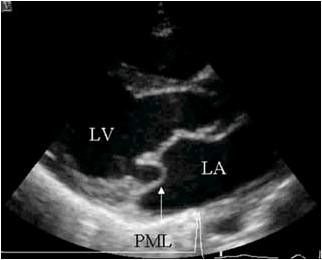

Itt egy tipikus kép egy négykamrás szakaszról, amely szerint az oroszországi echokardiográfusok többsége egyértelműen előidézi a prolapsus MK-t:

Ha a bal szívét vázolja, az orosz doktor-echokardiográfus szokásos akciói a következők:

Tartott egy egyenes vonal a bázis a szélén a elülső betegtájékoztató a mitrális billentyű (PSMK), majd a mért milliméterben elhajlást központ és abban következtetést a jelenléte a beteg elülső betegtájékoztatót előesés MK és annak mértékét.

Ez szerint a legtöbb ehokardiografistov Oroszország szükséges és elégséges a termelés süllyedés diagnózis egy (csúcsi) helyzetben a szelep néz ki, mint egy álla Peter Griffin a híres rajzfilm:

Süllyedés, vagy megereszkedett, az egyik vagy mindkét mitrális szisztolés fázis alatt tartják igaz csak akkor, ha be van jegyezve két echokardiográfiás helyzetben :. Apical négy kamra és parasternalis a hosszanti tengelye mentén a bal kamra „End quote.

Itt van a kutya eltemetve, kedves kollégák, echokardiográfusok. A parasternal helyzetben az úgynevezett "prolapsusok" 99% -a azonnal levágódik.

Gyakran láttál ilyen képet egy parasternal helyzetben? Nem.